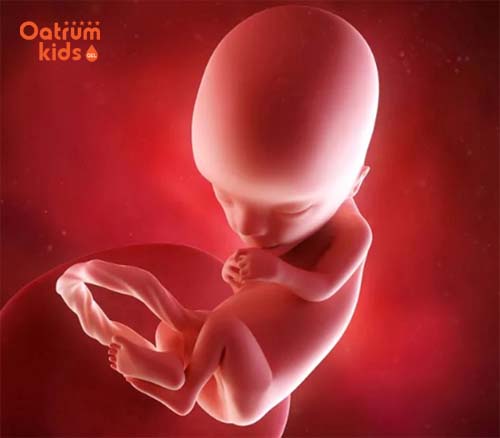

Theo các chuyên gia y tế ở tuần thứ 13 của thai kỳ bé yêu đã biết cau mày, nheo mắt, biết nhăn mặt, có thể tự mút ngón tay cái của mình. Nhờ có xung não mà cơ mặt của bé yêu đã có thể tự thể hiện một số các biểu hiện của nét mặt. Thậm chí nếu siêu âm đúng vào lúc con đang mút tay thì mẹ cũng có thể nhìn thấy được điều này.

Thai nhi 13 tuần tuổi đã biết nhăn mặt, cau màu, thể hiện rõ nét mặt.

Một bước tiến quan trọng nữa khi thai nhi tuần 13 đó là bé đã lớn lên rất đáng kể cả về kích thước cũng như các cơ quan bên trong. Kích thước cơ thể của bé lúc này đã tăng gấp 3 lần so với ban đầu, bé có kích thước bằng quả đậu Hà Lan, chiều dài khoảng 8-9cm tính từ đầu tới mông, cân nặng khoảng 30-43g.

Đồng thời ở giai đoạn này phần đầu và thân của bé đã trở nên tương đối cân bằng hơn, mẹ có thể nhìn rõ được sự liên kết giữa đầu cũng như cổ của bé qua hình ảnh siêu âm.

Hình ảnh thai nhi 13 tuần tuổi lúc này rất rõ rệt, bác sỹ có thể soi được biểu cảm khuôn mặt bé, hành động và cử chỉ của bé. Thậm chí chỉ vào cuối tuần thai thứ 13 là cánh tay của bé sẽ có chiều dài cân đối với thân hình. Trên cơ thể con cũng sẽ mọc thêm một lớp lông tơ siêu mịn, các tế bào tóc cũng đang bắt đầu hình thành.

Hoạt động của bé ở tuần thai thứ 13 cũng diễn ra liên tục không ngừng, bé thường xuyên thực hiện những cú đấm và đá, xoay chuyển mình, trườn mình. Nhưng vì đôi bàn tay và chân của con vốn rất nhỏ nên mẹ chưa cảm nhận rõ nét được mà thôi.